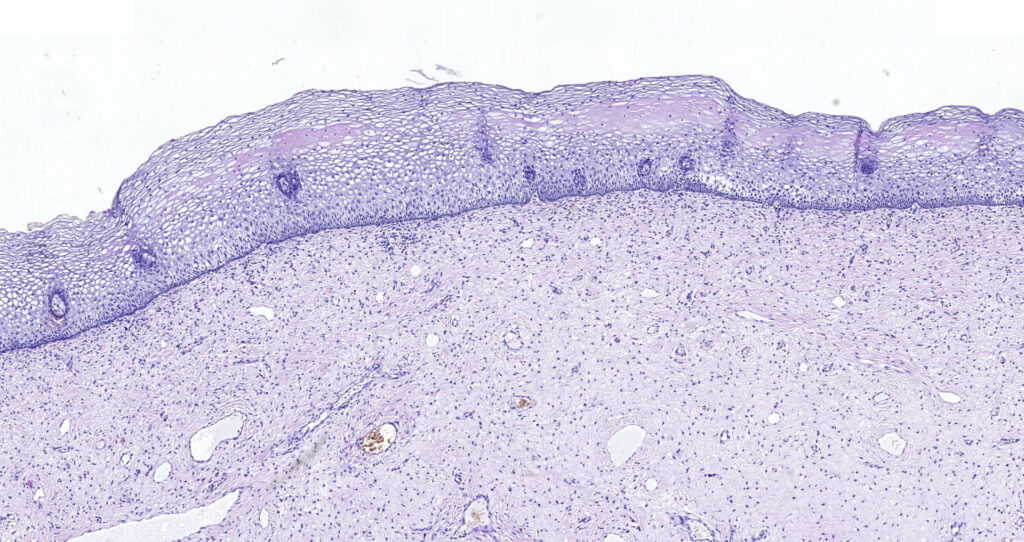

We are happy to announce our new service for our Clients. From the 1st of September, 2020 BioPartners offers you high quality virtual slides (whole slide images) of our banked FFPE samples. Our archive contains more than 1000 scanned images of different types of malignant neoplasms and normal tissues.

Besides, BioPartners offers slide scanning services to medical professionals and organizations at very affordable prices. What you need to do is to send us your glass slides with the completed order form and you will get them back along with the high-resolution and extra-quality virtual slides. Digital slides are either delivered on a DVD (in case of 1-2 glass slides) or an external hard drive. The slide viewing software will be provided as well. Scan type: illumination – bright field, objective magnification – 20x. Approximate size of the digital slide will be between 700MB and 2.5Gb. On your request, your FFPE (formalin fixed, paraffin embedded) or TMA tissue sample can be microtomed and H&E stained.